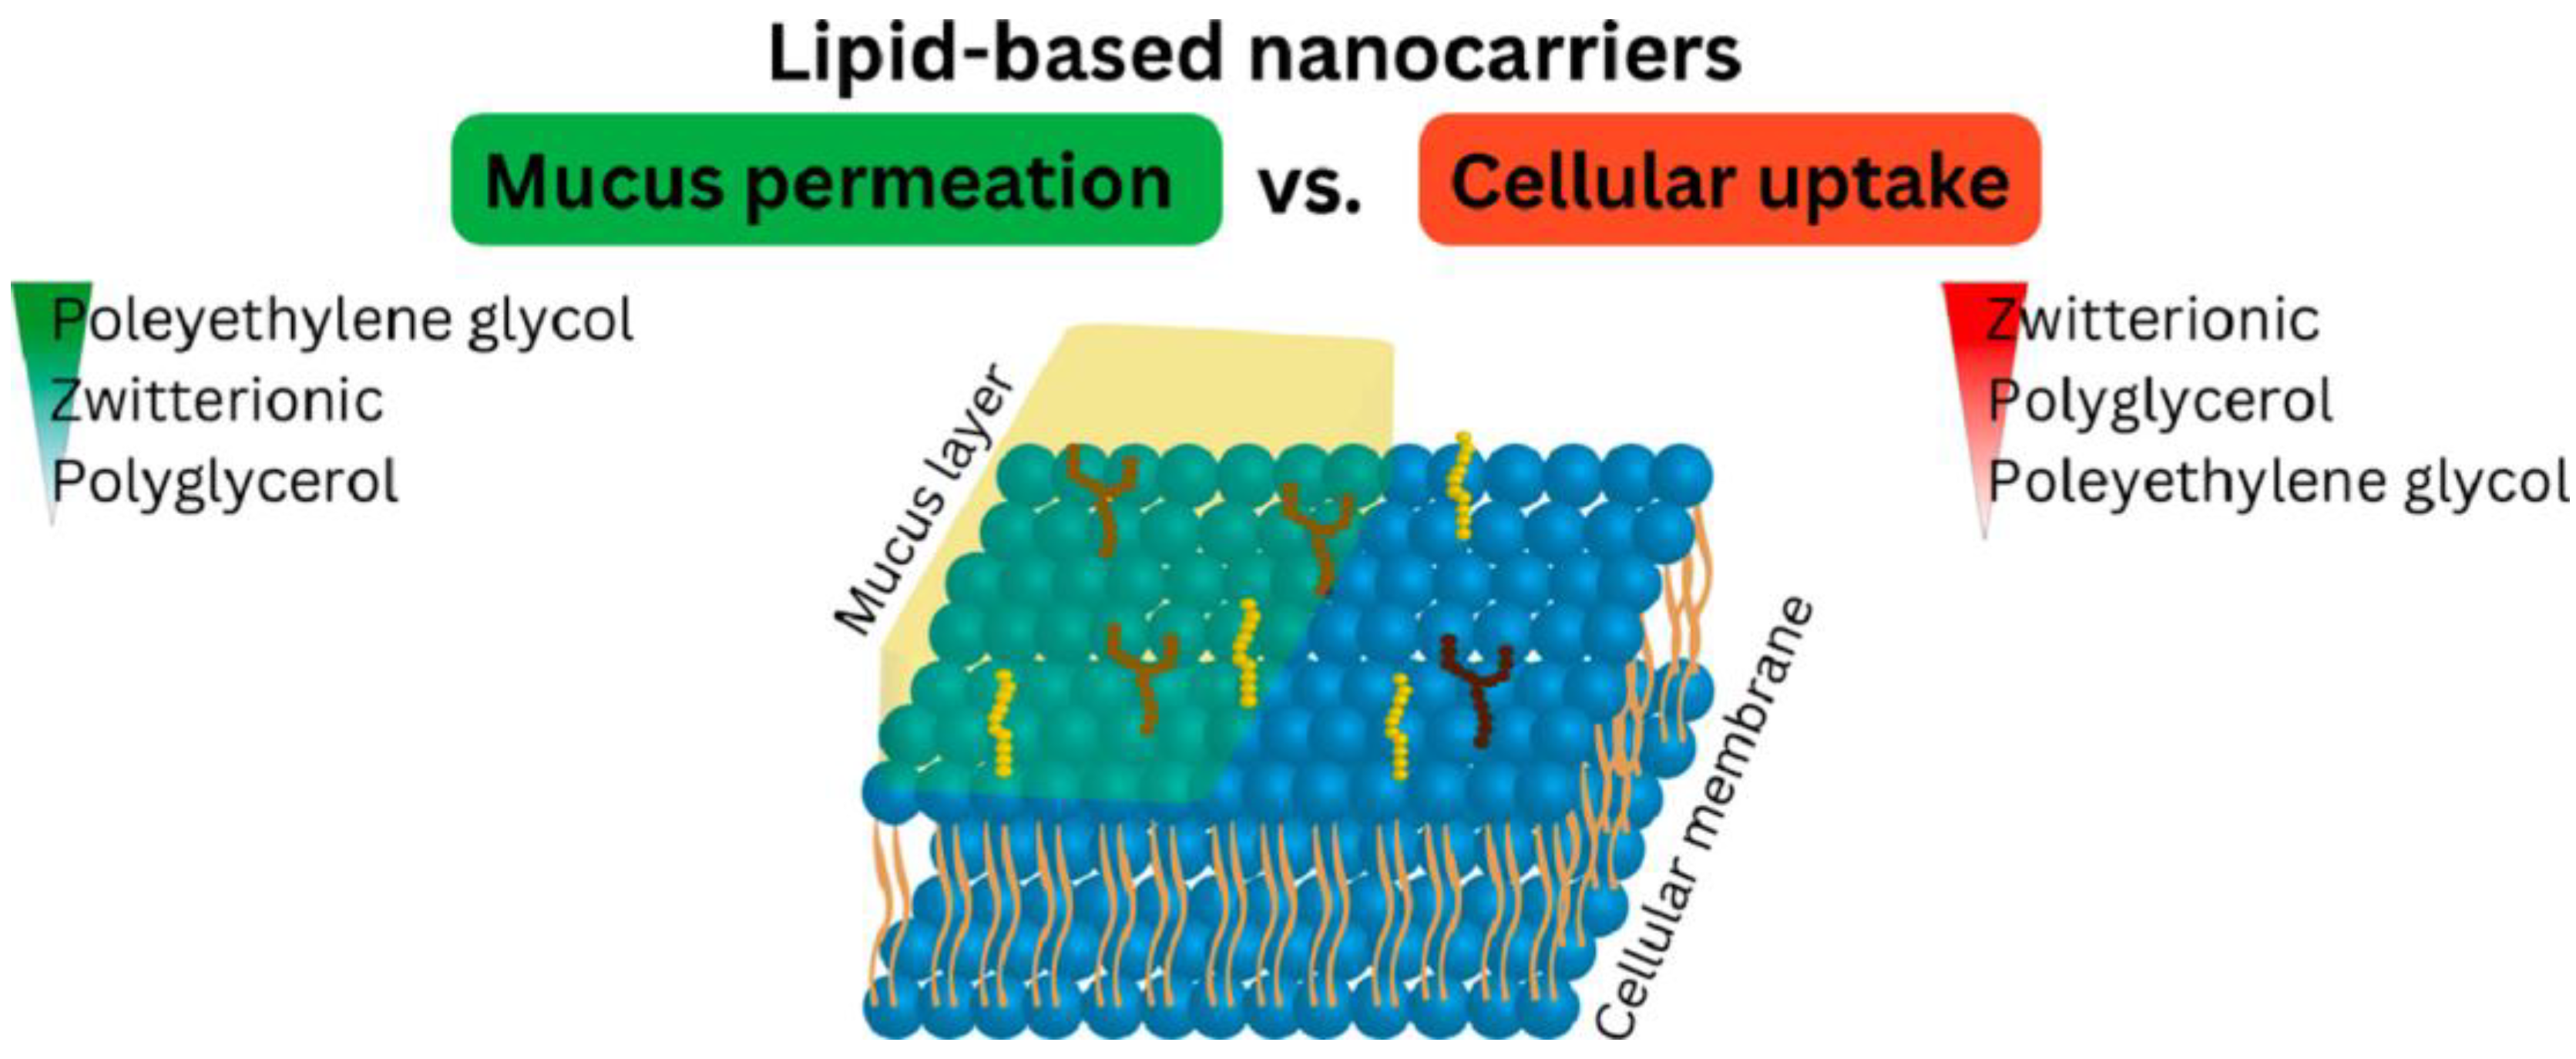

- Haddadzadegan, S.; Dorkoosh, F.; Bernkop-Schnürch, A. Oral Delivery of Therapeutic Peptides and Proteins: Technology Landscape of Lipid-Based Nanocarriers. Adv. Drug Deliv. Rev. 2022, 182, 114097. [Google Scholar] [CrossRef] [PubMed]

- Veider, F.; Knoll, P.; Jörgensen, A.M.; Stengel, D.; Bernkop-Schnürch, A. Oral Drug Delivery: Influence of Mucus on Cellular Interactions and Uptake of Lipid-Based Nanocarriers in Caco-2 Cells. Acta Biomater. 2023, 167, 416–424. [Google Scholar] [CrossRef] [PubMed]